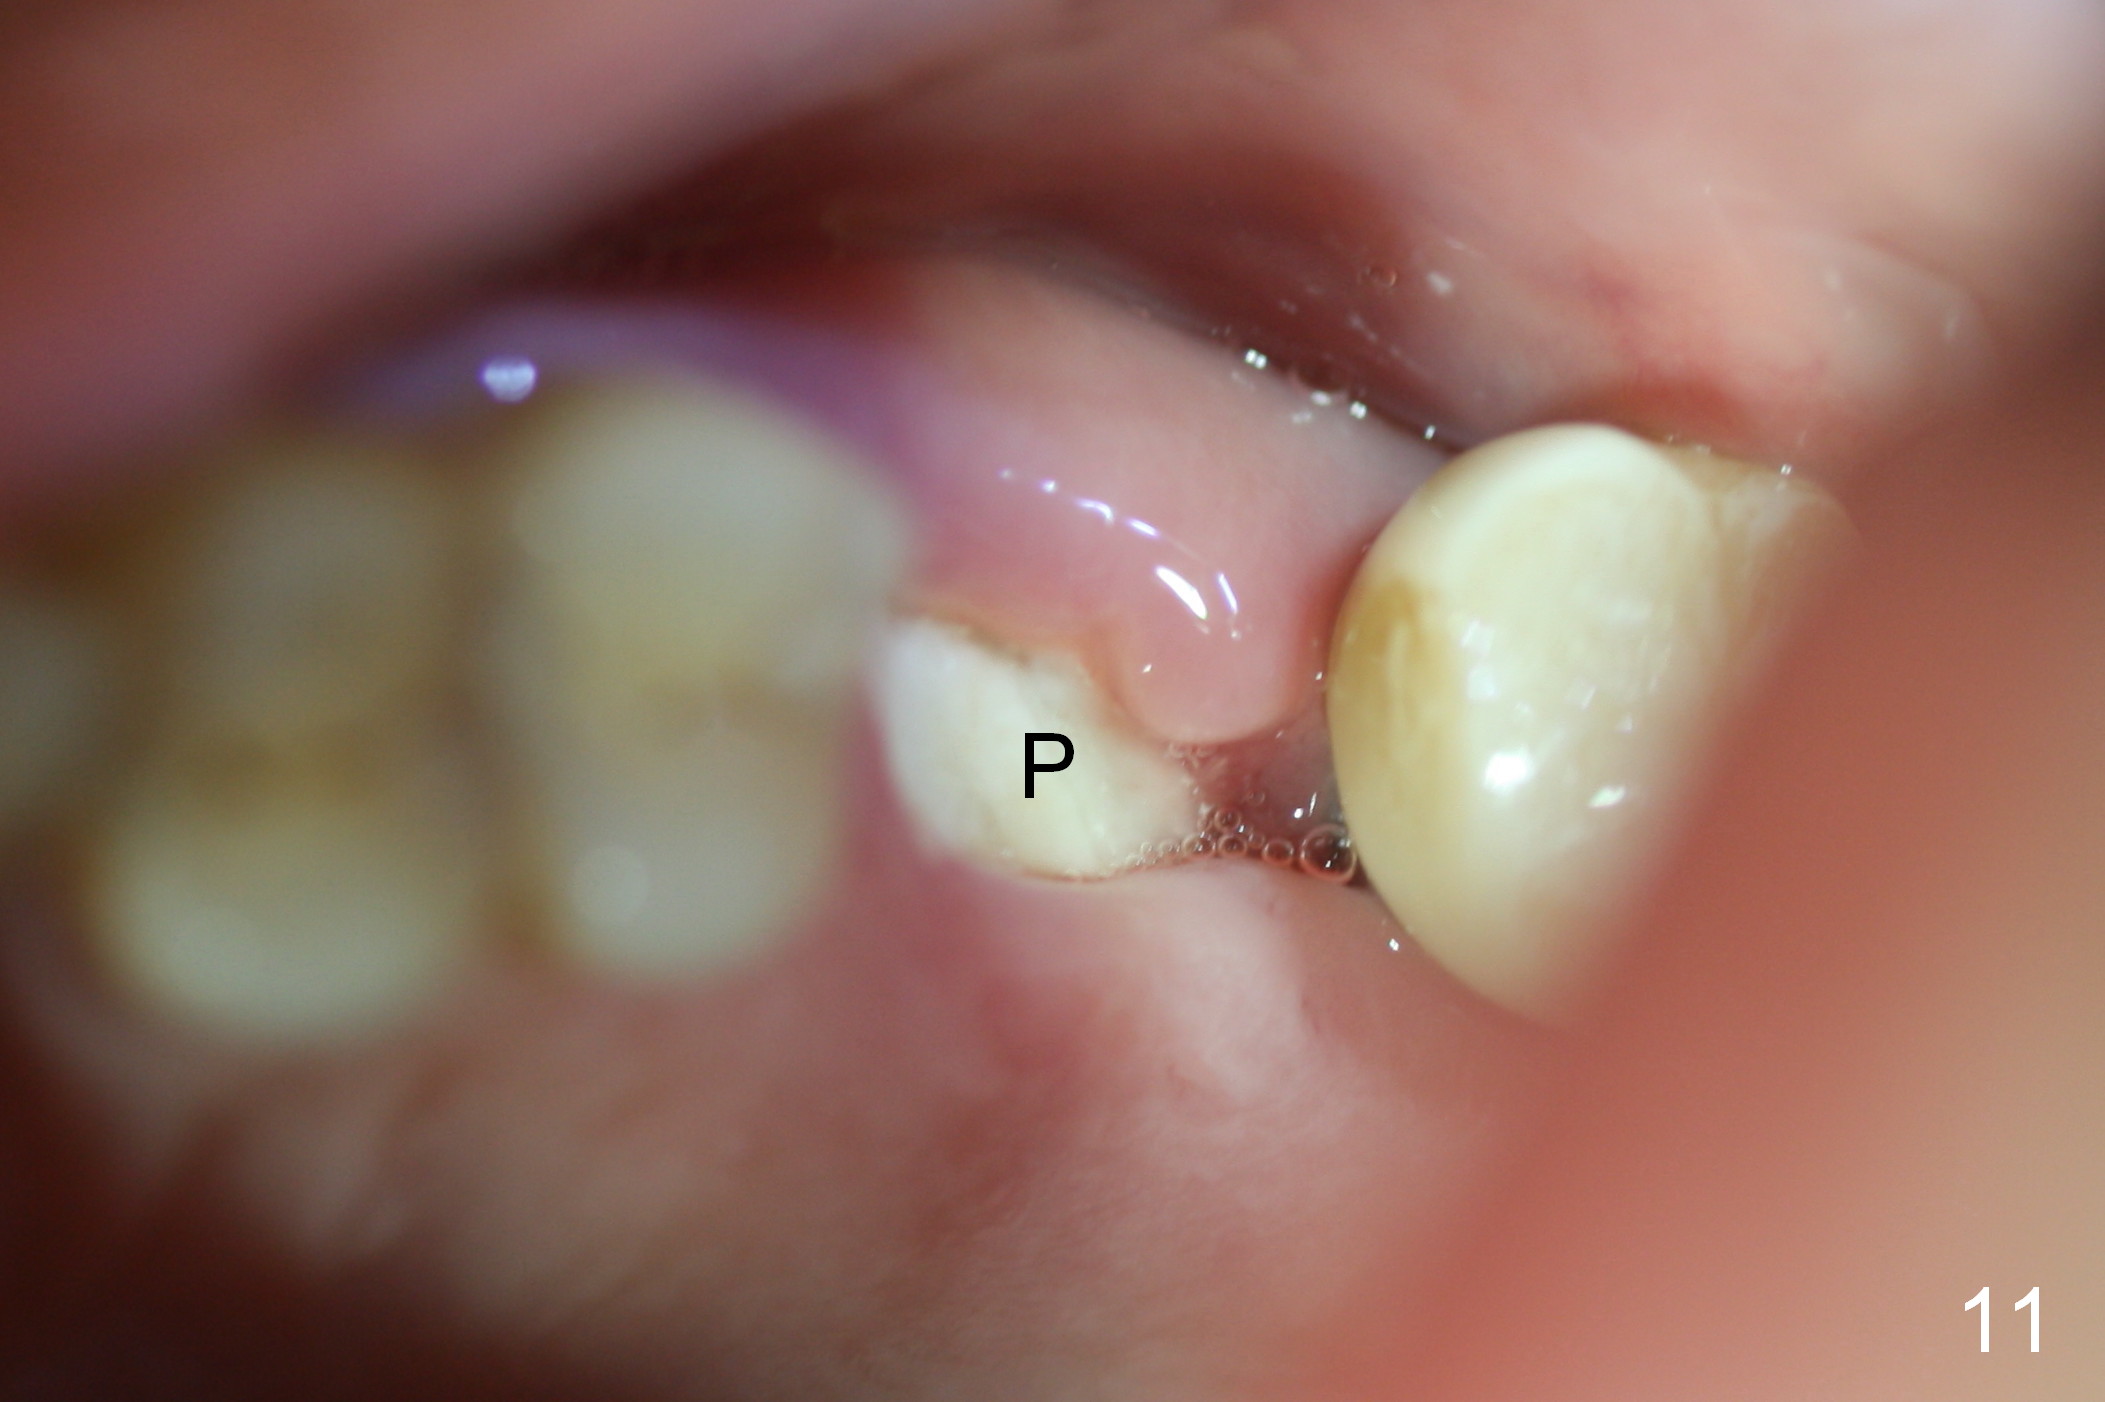

There is no palatal erythema or edema 9 days post extraction (Fig.10 *) with shrinkage of the socket opening. The Osteogen plug remains in place (Fig.11 P). The patient will return for implant placement 6 months post socket preservation.